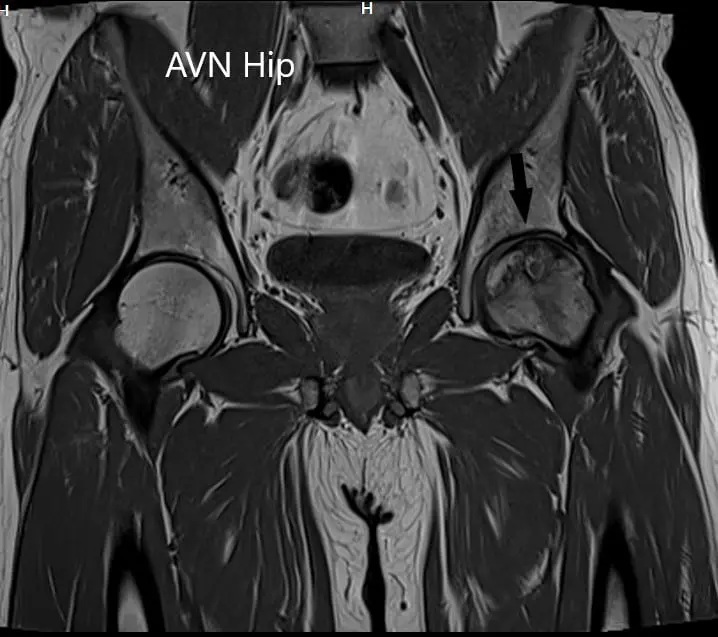

An MRI was obtained which suggested avascular necrosis of the left hip stage 3. There were altered signal intensity and bone marrow edema.

T1WI coronal section of MRI showing AVN hip.